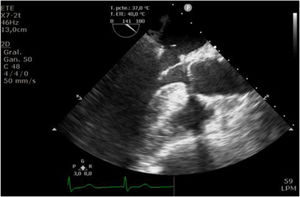

Quirúrgicamente se realizó la canulación en arco aórtico (generalmente se realiza en aorta ascendente, pero debido a la presencia de una extensa placa calcificada en aorta ascendente junto con inestabilidad hemodinámica se optó por canular en arco aórtico) y bicava, entrando en circulación extracorpórea (CEC) con heparinización sistémica previa. Se realizó clampaje aórtico y se administró cardioplejia de forma anterógrada. Se realizó atriotomía derecha, con visualización del orificio de punción transeptal y apertura del septo, consiguiendo una exposición valvular extrayéndose el dispositivo sin dificultades (fig. 3). Se revisó la válvula mitral que presentó un pseudoprolapso del P1, realizándose una anuloplastia mitral mediante la colocación de un anillo Sorin MeMO-3D de 28mm (Corcym Srl, Salauggia VC, Italia)TM, más plicatura del velo posterior (P1) (fig. 4) con cierre posterior del septo y de la AD. Finalmente se cerró la orejuela mediante la colocación de Atriclip 40 (AtriCure, Mason, Ohio, EE.UU.)TM. Posteriormente se desclampó y se desinstauró progresivamente la CEC, con necesidad de apoyo hemodinámico con DBT a 5μg/kg/min y NAD a 0,08μg/kg/min en perfusión continua. El paciente salió en ritmo sinusal y se dejaron cables ventriculares de marcapasos, se revirtió al paciente con protamina e.v. y se dejaron tres drenajes mediastínicos. El tiempo de CEC fue de 73min y el tiempo de clampaje de 54min. Durante la cirugía se transfundieron dos concentrados de hematíes y dos concentrados de plaquetas. Posteriormente se trasladó a la unidad de cuidados intensivos cardíacos (estancia de 48h), donde requirió tratamiento vasoconstrictor con NAD y DBT a dosis de 0,05μg/kg/min y 4μg/kg/min, respectivamente, por tendencia a la hipotensión. Inicialmente fue dependiente de marcapasos (VVI), ya que persistió en FA bloqueada con ritmo de escape nodal a 50lpm; posteriormente presentó un ECG con silencio auricular que revirtió con amiodarona manteniéndose finalmente en ritmo sinusal. A las 48h fue trasladado a la unidad de postagudos del corazón (UPAC), donde estuvo ingresado durante 20 días, subiendo a planta de hospitalización convencional, hasta completar un total de 30 días de ingreso, siendo dado de alta al domicilio con recuperación ad integrum.